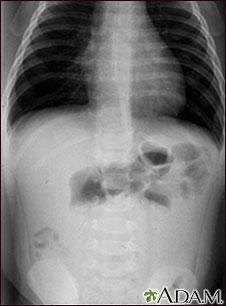

腸套疊,這個聽起來陌生的詞彙,卻是兒童急診室裡常見的急症之一。它就像一場腸道的「內捲」,一段腸子套入另一段腸子,造成腸道阻塞,甚至可能導致腸壁壞死。診斷的關鍵,在於醫師的敏銳觀察與經驗,以及精準的影像學檢查。透過超音波,醫師可以清晰地看到腸道套疊的影像,就像一個「靶心」或「甜甜圈」的模樣。而X光檢查則能幫助排除其他可能的原因,例如腸阻塞或穿孔。